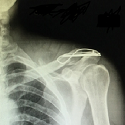

Misplaced left internal jugular venous catheter with an exceptional location

Hassen Ben Ghezala, Najla Feriani

PAMJ. 2016; 24: 305. Published 10 August 2016